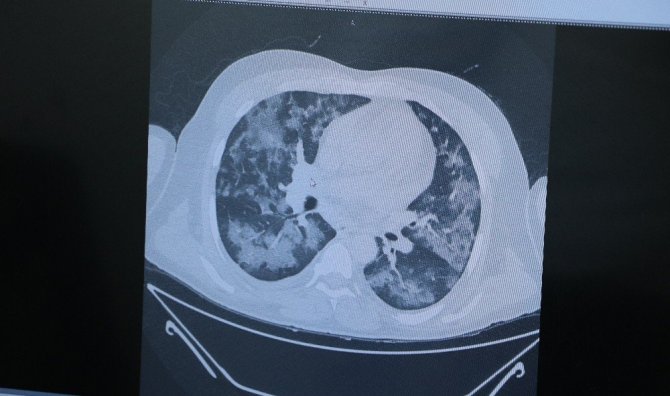

Tedavi altındaki 5 kişinin akciğerlerini inceleyen Prof. Dr. Özkaya, "Hâlâ bu hastalığa inanmayanlar olabilir. Bu hastalığın yapay, suni bir medya haberi olduğu söyleniyor. Size şu an 5 hasta örneği göstereceğim. 5'i de şu an yatıyor ve yaşam mücadelesi veriyor. Okulda bir yarışma düzenlendiğini düşünün, tüm Türkiye'de okullar arası bir yarışma yapılıyor ve yarışmada bir resim yapmanızı istiyorlar. Tüm Türkiye'deki bütün okullardaki öğrenciler birbirinden bağımsız olarak aynı resmi yapıp getiriyorlar. Böyle bir şey mümkün mü? 58 yaşında bir hastamız, akciğerinde yaygın Covid-19 lekesi. Birbirinden bağımsız ayrı insanlar. Yine aynı tabloyla gelen başka bir hasta ve yine aynı tabloyla yatan başka bir hasta. Bu hastaların hepsi şu an yaşam mücadelesi veriyor ve büyük oranda tedavi edebildiğimiz hasta grupları. Böyle bir tabloyu biz bugüne kadar hiç görmedik. Bugüne kadar yaşayan en yaşlı doktorlar bile akciğerleri böyle etkileyen bir bulaş hastalığı görmedi. Bu bir gerçektir, bu bir yaşadığımız hayat tecrübesidir. Lütfen daha duyarlı olalım" ifadelerini kullandı.